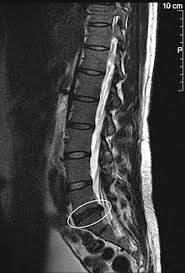

Bandscheiben op lws 4 5. Sie kommen meist zwischen den Wirbeln LWK Lendenwirbelkörper 45 und LWK 5SWK 1 Sakralwirbelkörper vor an der vorletzten und letzten Bandscheibe. Bandscheibenvorfälle sind Teil einer natürlichen Abnützung des Gewebes. Drückt der Gallertkern auf einen Rückenmarksnerven leiden Betroffene unter starken Rückenschmerzen die teilweise bis in Arme und Beine ausstrahlen.

Auch durch Vernarbungen nach der OP kann es zu Schmerzen oder Einschränkungen der Bewegung kommen. Merkblatt zur Nachbehandlung Operation an der Lendenwirbelsäule 1 4 Merkblatt zur Nachbehandlung Operation an der Lendenwirbelsäule Sehr geehrter Patientin Was Sie wissen sollten Sie leiden an einer degenerativen Erkrankung einer oder mehrerer lumbaler Bandscheiben Bandscheibenvorfall Spinalkanalstenose Wirbelgleiten. Nach einem Bandscheibenvorfall gilt es gezielt die Muskulatur im betroffenen Bereich zu stärken.

Wenn die Physiotherapie und Medikamente nicht mehr helfen und die Schmerzen zu stark sind oder wenn der Druck auf die Nerven Ausfälle verursacht Taubheit Muskelschwäche Lähmung sollte eine Operation in Betracht gezogen werden. Bandscheibenvorfall LWS Übungen - Hier findest du 5 effektive Übungen bei einem Bandscheibenvorfall in der Lendenwirbelsäule inkl. Es geht mir zur Zeit nicht gut mache mir auch große Sorgen wie es wird in den nächsten Tagen und Wochen mit den Schmerzen und Beschwerden. Ich wurde am 4. Frank aus München in. Probieren Sie es selbst aus. Sie kommen meist zwischen den Wirbeln LWK Lendenwirbelkörper 45 und LWK 5SWK 1 Sakralwirbelkörper vor an der vorletzten und letzten Bandscheibe. Die Bandscheiben der Wirbelsäule übt eine Art Stossdämpferfunktion aus und dient der Elastizität und der Beweglichkeit der Wirbelsäule. Lendenwirbel und dem 5.

Die Bandscheibenvorfälle an der Lendenwirbelsäule sind die häufigsten Bandscheibenvorfälle an der Wirbelsäule. In der Regel verschwinden die Schmerzen zwar nach der OP es kann aber immer sein dass sich Symptome nicht zurückbilden. Wenn die Physiotherapie und Medikamente nicht mehr helfen und die Schmerzen zu stark sind oder wenn der Druck auf die Nerven Ausfälle verursacht Taubheit Muskelschwäche Lähmung sollte eine Operation in Betracht gezogen werden. 3053 Beiträge ø047Tag Hallo vor 1 Woche hatte ich eine große Bandscheiben-OP. Wie der Bandscheiben-Vorfall Prolaps ist die Bandscheiben-Vorwölbung Protrusion besonders häufig in der Etage bei L4L5 zwischen dem 4. Bandscheibenvorfall 4-5 Lendenwirbel Hey S-A2011 danke für Deine Erzählung. Alleine in Deutschland werden jährlich ungefähr 150000 Bandscheibenvorfälle operativ behandelt.